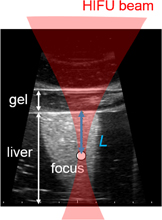

Standard image High-resolution imageSixteen frames (corresponding to one period of LMI oscillation) of RF data obtained by an ultrasound scanner were acquired within 0.05 s in every 1 s. The computation time for data processing including cross-correlation was within 0.9 s. This sequence is shown in Fig. 6. HIFU ablation time was controlled using a gate circuit based on the results of LMI. The target was porcine liver tissue embedded in polyacrylamide gel. The experiments were conducted at room temperature. In this experiment, the AM frequency was 168 Hz. The HIFU frequency and intensity were 2.2 MHz and 1.2 kW/cm2, respectively. The beam propagation distances L shown in Fig. 7 are 10, 20, and 30 mm. The experiments were conducted as follows:

Standard image High-resolution imageFig. 7. Beam propagation distance L on a B-mode image.

Download figure: